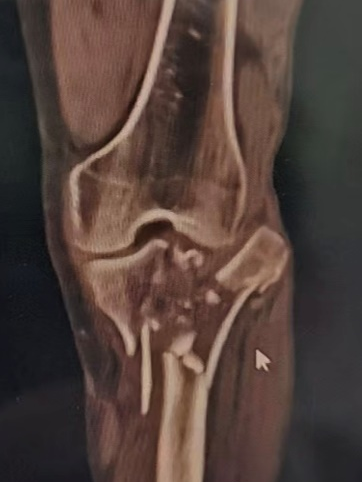

回溯至春节期间,63岁的李大爷因意外导致左下肢遭受重创。经外院检查,诊断为左侧胫骨平台及腓骨近端严重粉碎性骨折,并伴有复杂的关节脱位、韧带及半月板多发损伤。伤后肢体迅速肿胀,疼痛难忍,为求更加有效的治疗,家属四处寻医,心急如焚,四处打听,最终辗转慕名来到我院。

▼术前图像